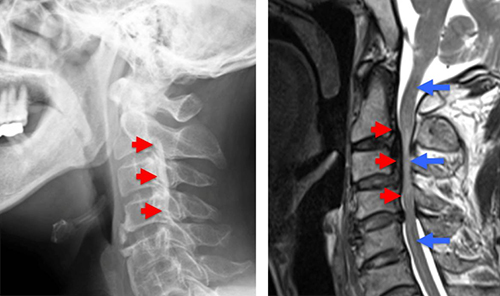

3. 頚椎後縦靱帯骨化症(OPLL)

特徴

中高年男性に多く、進行性の疾患です。

早期診断が重要で、進行すると手術が必要になることがあります。

MRIやCTで骨化の範囲を確認します。